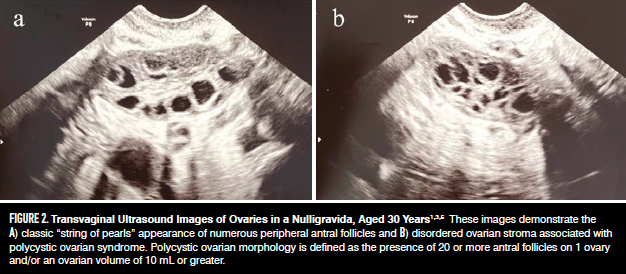

El PCOM se define como la presencia de folículos antrales mayores o iguales a 20 por ovario (antes 12) o un volumen mayor o igual a 10 mL por ovario, de acuerdo con las guías internacionales más recientes (Figura 2 ).